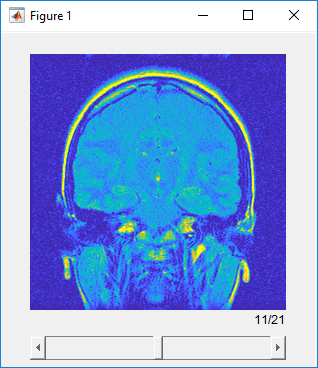

Когда это открывается, sliceViewer отображения объекта среднее изображение в стеке в направлении заданы sliceDirection. Используйте ползунок, чтобы перейти через объем и просмотреть отдельные срезы.

sliceViewer( отображает шкалу полутонов или объем RGB V)V на рисунке. Фигура включает ползунок, который можно использовать, чтобы просмотреть отдельные срезы объема.